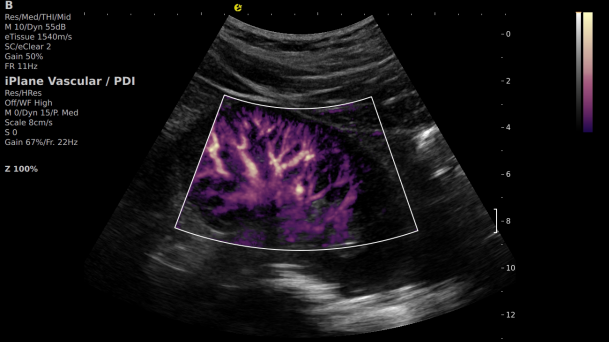

2) 可检测20-50μm级细小血管低速血流信号,能看清头发丝1/2粗细的微血管;

微米级超高分辨率血流信号显像

超微视血流显像评估肾移植术后灌注情况

这一项无创、无辐射操作简便且无需造影剂的黑科技,相当于用"高速摄像机"记录血液细胞的运动轨迹,让血管并发症"无处遁形。